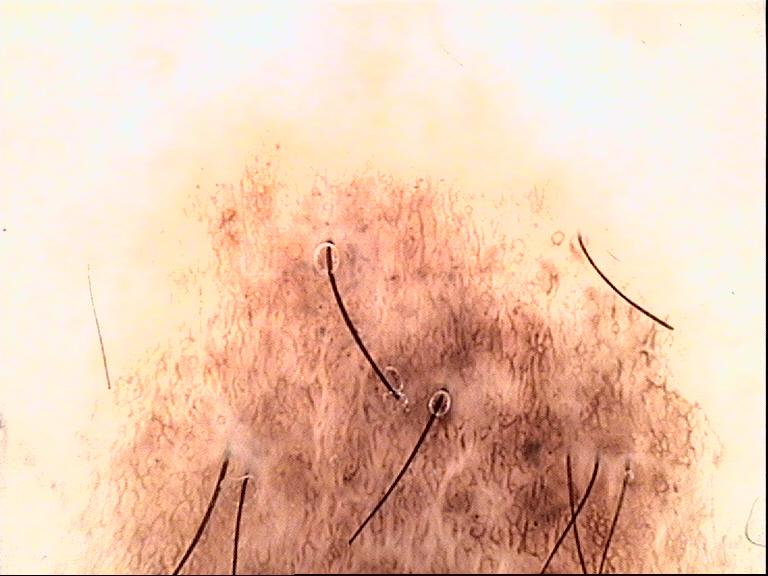

Skin lesion datasets provide essential information for understanding various skin conditions and developing effective diagnostic tools. They aid the artificial intelligence-based early detection of skin cancer, facilitate treatment planning, and contribute to medical education and research. Published large datasets have partially coverage the subclassifications of the skin lesions. This limitation highlights the need for more expansive and varied datasets to reduce false predictions and help improve the failure analysis for skin lesions. This study presents a diverse dataset comprising 12,345 dermatoscopic images with 40 subclasses of skin lesions, collected in Turkiye, which comprises different skin types in the transition zone between Europe and Asia. Each subgroup contains high-resolution images and expert annotations, providing a strong and reliable basis for future research. The detailed analysis of each subgroup provided in this study facilitates targeted research endeavors and enhances the depth of understanding regarding the skin lesions. This dataset distinguishes itself through a diverse structure with its 5 super classes, 15 main classes, 40 subclasses and 12,345 high-resolution dermatoscopic images.

Yilmaz, A., Yasar, S.P., Gencoglan, G. et al. DERM12345: A Large, Multisource Dermatoscopic Skin Lesion Dataset with 40 Subclasses. Sci Data 11, 1302 (2024). https://doi.org/10.1038/s41597-024-04104-3